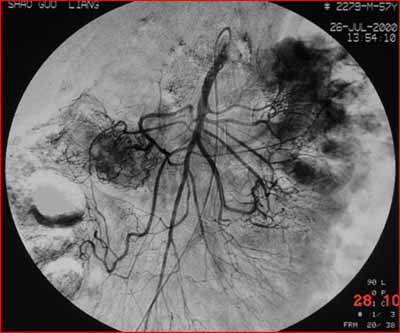

(結(jié)腸動脈造影:腫瘤染色明顯。通過造影明確供血動脈,進行腫瘤區(qū)域的化療灌注。)

據(jù)統(tǒng)計,結(jié)直腸癌術(shù)后約有40%的人會出現(xiàn)肝臟轉(zhuǎn)移,對于已有肝臟轉(zhuǎn)移的患者,傳統(tǒng)的手術(shù)更是無法徹底治療。這類病人則可用介入治療:先將幾種最有效的抗癌藥搭配在一起,然后通過導(dǎo)管技術(shù),找到腫瘤的供養(yǎng)動脈,把抗癌藥和栓塞劑直接注入腫瘤組織。這種療法主要有兩大優(yōu)勢:一方面將高濃度的藥物直接作用于局部,發(fā)揮最大的抗腫瘤作用,對全身毒副作用小,絕大部分患者能接受治療;另一方面,還可將腫瘤的供血血管阻塞,使腫瘤失去血供而“餓死”。對于術(shù)前尚未有明確肝轉(zhuǎn)移的患者,術(shù)前若用介入治療,可消滅“隱性的轉(zhuǎn)移”(單個腫瘤細胞的轉(zhuǎn)移),配合手術(shù)和術(shù)后的全身化療,復(fù)發(fā)率顯著下降。而對于術(shù)前已有肝臟轉(zhuǎn)移的患者,術(shù)前的介入治療可使轉(zhuǎn)移灶縮小,為手術(shù)提供良好的機會,再配合術(shù)后的全身化療,患者的生存率顯著提高??傊槿胫委煹某霈F(xiàn),為提高結(jié)直腸癌的治療效果、延長患者的生命,起到很好的作用。